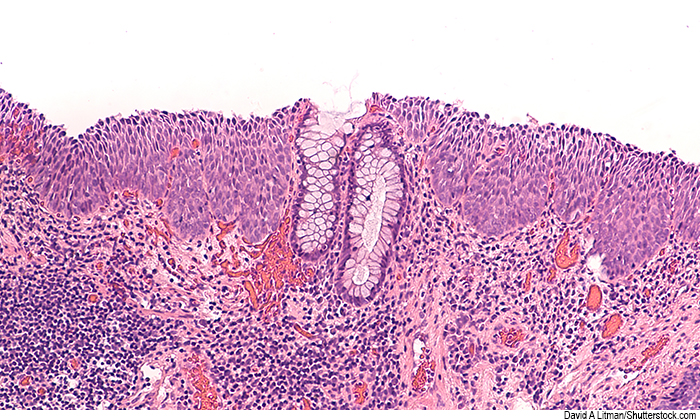

Like cervical cancer, anal cancer is caused by human papillomavirus (HPV), leading to precancerous high-grade squamous intraepithelial lesions that can progress to cancer.